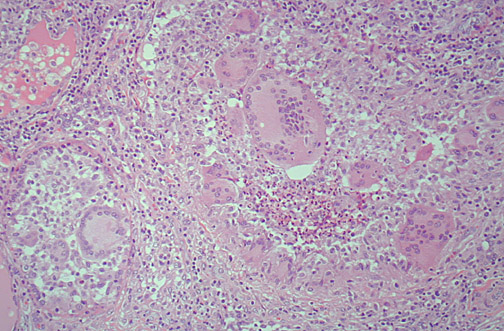

Image 8.2

What are the findings seen here at medium power?